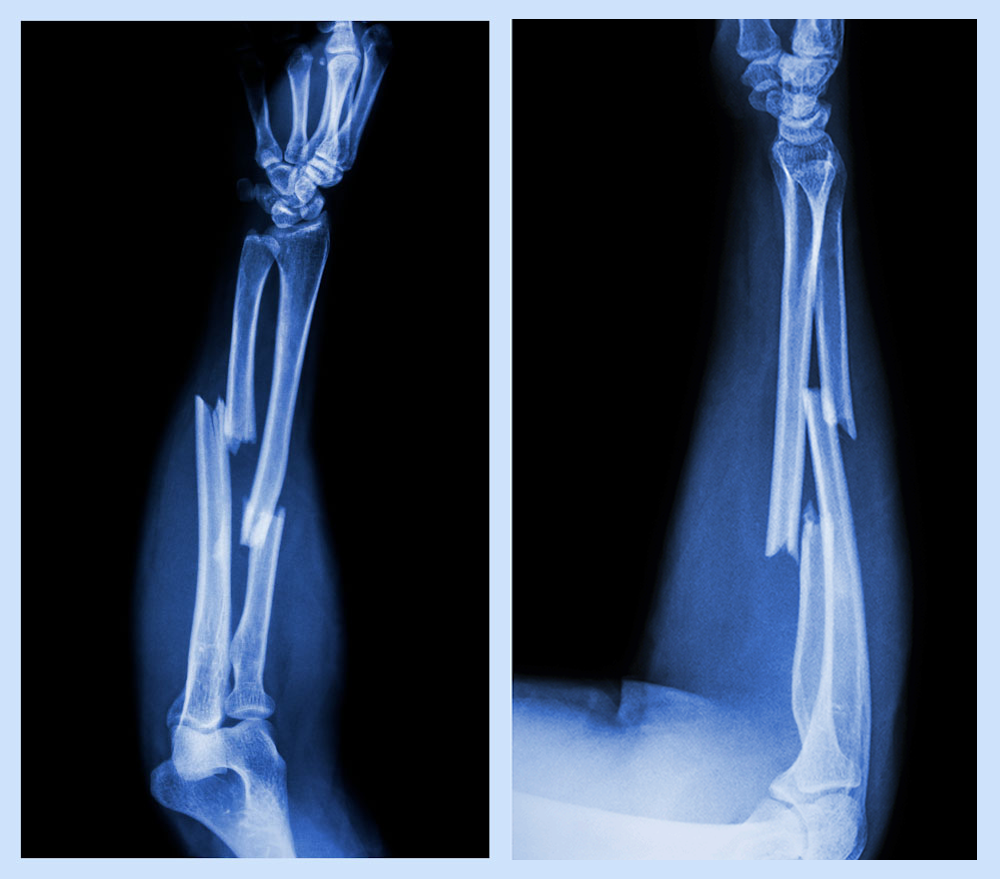

Ulnar and Radial Fracture

Anteroposterior and lateral radiograph of a dislocated proximal forearm fracture. Note that both the ulnar and radial bones were fractured. An open reduction and plate fixation of the fracture was performed two weeks ago. See the orthopedist’s discharge notes |